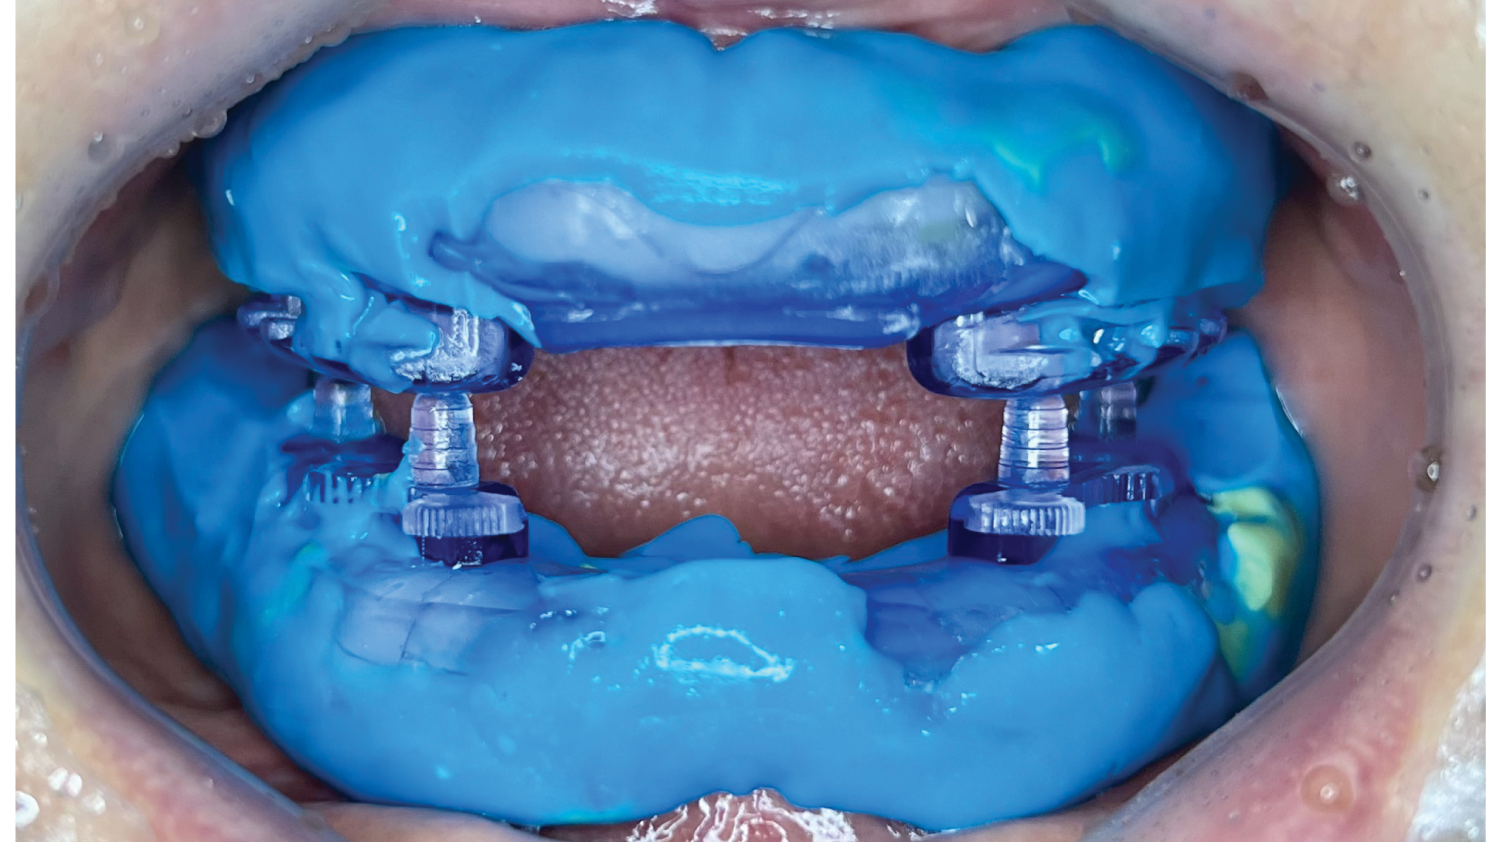

Course Overview

This course presents simplified yet clinically precise workflows for edentulous patients, enhancing both efficiency and patient comfort. Using the JB Tray, participants will learn how to combine custom tray fabrication, final impression, and jaw relation records in a single appointment, supported by digital processing and a live demonstration.

This course presents simplified yet clinically precise workflows for edentulous patients, enhancing both efficiency and patient comfort. Using the JB Tray, participants will learn how to combine custom tray fabrication, final impression, and jaw relation records in a single appointment, supported by digital processing and a live demonstration.

The program also introduces the JB Fork system, which integrates CBCT imaging and anterior reference points to enable one-step surgical stent fabrication without repeated impressions. Through practical demonstrations, attendees will see how this approach streamlines implant surgery while maintaining accuracy. The course concludes with insights into plasma surface treatment in implantology, highlighting its role in advancing clinical outcomes.

One-Step Denture with JB Tray

• Fundamentals of jaw relation records in edentulous patients: Determining VD, CR, and the occlusal plane

• The concept of closed-mouth impression and understanding the appropriate external form of dentures

• One-step clinical workflow with the JB Tray: From custom tray fabrication to final impression and jaw relation record in a single appointment

• Digital processing of impressions obtained with the JB Tray

• Live demonstration with an edentulous patient

JB tray clinical procedure (Prof. Huh) |

| 10:00AM – 11:00AM |

Clinical application with an edentulous patient (Real patient) from impression to scanning with an intraoral scanner. (Prof. Huh) |